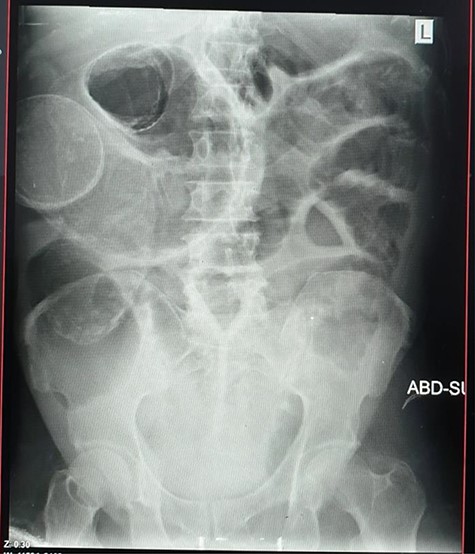

Radiological investigations

Plain abdominal X-ray (supine) showed grossly dilated large bowels (Fig. 1), and a chest X-ray showed a right-sided pneumothorax, which was managed by a thoracostomy tube (Fig. 2).